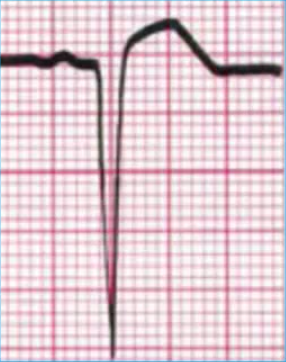

Principales cambios Electrocardiográficos del Infarto Agudo al Miocardio

Se observan en el registro de las 12 derivaciones

Necrosis

->30 min.-Irreversible-QS-R altas como cambio en espejo